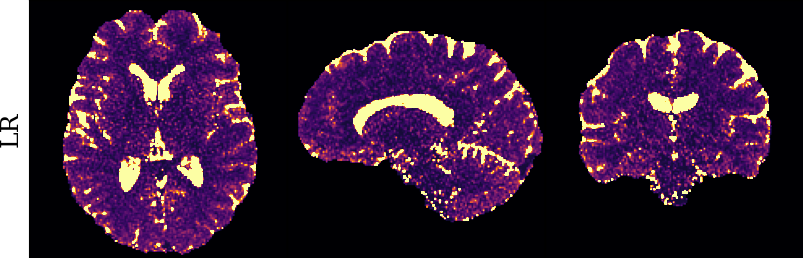

To monitor performance progress, we mapped TSMI to Q-Maps every five epochs. To mitigate the lengthy processing times associated with Dictionary Matching, we implemented a fully connected network to directly map TSMI to Q-Maps [5], significantly reducing processing time. However, for the final assessment, we employed DM on all techniques at the conclusion of the training process (epoch 500). We report in Table 1 the Mean Average Percentage Error (MAPE) of T1/T2 maps, and Peak Signal-to-Noise Ratio (PSNR) and Structural Similarity (SSIM) Index for T1/T2 and normalised PD. To accompany these metrics we also offer in Fig. 2 the reconstructed T1 and T2 maps for the different approaches.

The training and validation loss (Fig. 1) served as valuable guides for architecture and training design. To demonstrate this, we selected a subset of experiments in which we kept certain variables fixed and only modified the one under inspection. From Fig. 1 (a)-(d), MAPEs curves show there is a clear setting with the preferred performance. Specifically, from Fig. 1a, it is evident that using DRUNet yields a clear improvement over the original architecture. This could be attributed to the utilisation of residual units in addition to other architecture differences, such as the choice of upsampling operator (transpose convolution for DRUNet and trilinear for DIP). The choice of input (Fig. 1b) demonstrated a consistent pattern among the tested options, with low rank (conjugate gradient) initialiser marginally outperforming the others. Fig. 1cshows that by epoch 100, stochastic approaches exhibit lower reconstruction errors compared to non-stochastic methods. For example, adaptive LR with stochastic training yields a combined MAPE of 61.40% (17.09% T1 and 44.31% T2) vs. 213.69% (35.50% T1 and 178.19% T2) for the non-stochastic method. This fast convergence is due to adaptive LR and stochastic updates across coils. Despite similar execution times ( 34 min for stochastic with adaptive LR vs. 32 min for non-stochastic with fixed LR), the rapid error reduction makes StoDIP more attractive for training.. To assess the early stopping of DIP models, a key element, we present Fig. 1d. The original work by Ulyanov et al. [21] used 2k iterations, while Hamilton et al. [12] used 30k. In contrast, our settings show StoDIP achieving competitive performance in under 500 epochs (4k iterations) on the entire volume. However, StoDIP can overfit to k-space measurements, affecting reconstruction accuracy, and thus the iteration at which it stops could have a greater impact. We show that adding a spatial penalty term addresses overfitting and instabilities. This is supported by the maps in Fig.2, supplementary material Figures 1-3, and metrics in Table 1. StoDIP reconstructions lack aliasing artifacts, and the TV regularizer (StoDIP + TV) further improves Q-Map reconstruction by reducing checkerboard artifacts observed in StoDIP outputs alone.